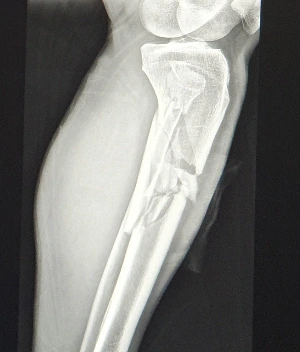

골절 상태

서귀포의료원 응급실에 도착하니 응급조치를 받는데, 아내가 왔다. 급히 달려온 아내를 보니 안쓰럽다. 엑스레이를 찍으려고 골절된 다리를 올리는데 눈물이 찔끔 나올 정도로 통증이 몰아친다. 낙상사고 현장에서는 핸드폰을 찾아야 살 수 있어 엉덩이로 움직일 때는 아픈 줄도 몰랐는데 구조된 후 응급실에서 액스레이에 몸을 올리는데 어마어마한 통증이 온몸으로 퍼진다.

손가락 탈구를 원상 조치하는데 왜 그리 아픈지 눈을 감고 아우성쳤다. 이마가 찢어져 6 바늘 꿰매는데 따끔거린다. 다리는 찢어진 부위를 꿰매고, 발부터 허벅지까지 붕대를 감고 긴 반깁스를 하였다. 간호사에게 다리 수술은 언제 하느냐고 물었더니 내일 할 것 같다는 대답이다. 응급조치를 끝내고 서귀포의료원에 입원하였다.

작년에는 낙상으로 갈비뼈에 균열이 생겨 입원했는데 수술 없이 약물 치료로 괜찮아졌다. 그런데 1년도 안돼 정강이뼈 골절을 당했으니 큰 수술과 재활이라는 긴 싸움이 시작되었다. 코로나 기간이라 병원의 면회도 금지되고, 간병인도 밖에 나가면 코로나검사 확인이 있어야 들어온다. 그래서 아내도 병원에 갇혔다.